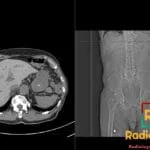

- Radiology Cases: Images with a to-the-point discussion highlighting the specific diagnostic criteria.

- Radiology Case of the Day Collection: Aunt-Minnie Board Cases for Rapid Review.

Latest Radiology Cases